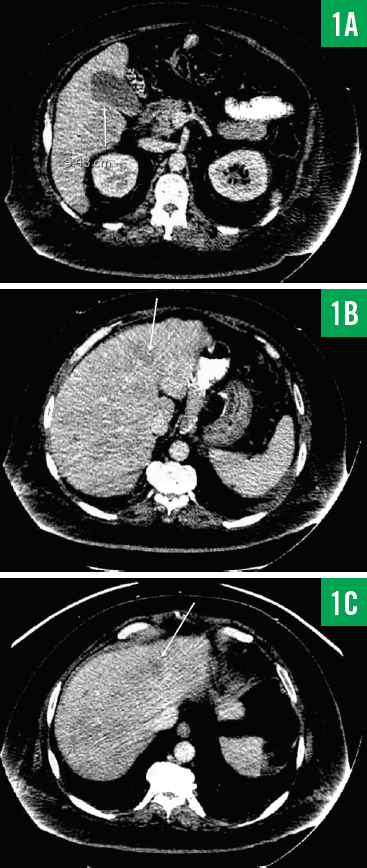

Computed tomography (CT) scans of the chest and abdomen/pelvis showed innumerable low-attenuation lesions scattered throughout the liver, with the largest measuring up to 5.5 cm in diameter (Figures 1A-1C); the lesions were likely related to metastasis. A questionable lesion was also noticed at the head of the pancreas (Figure 2), and the scan showed bowel-wall thickening involving the proximal descending colon (Figure 3).

Figure 1. CT scans of the patient’s abdomen/pelvis showing a 5.48-cm lesion involving the inferior aspect of the right lower lobe of the liver (1A) and additional smaller lesions involving the liver (1B and 1C).